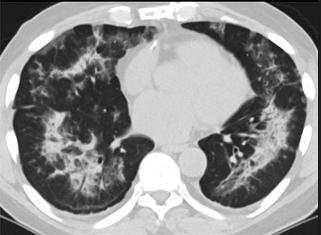

1、“白肺”是指肺部在影像学上出现的白色区域,主要由严重的病毒性肺炎等引起,预防以预警为主。“白肺”从医学上来说,有两种情况:原有肺部疾病:例如肺纤维化、肺结核等,肺部受到了损伤,在影像学上会出现白肺。

2、白肺是指肺部在影像学检查中呈现大片白色阴影的状态,通常代表肺部存在严重的炎症或感染。在肺炎诊断中,白肺往往意味着病情较为严重,需要引起高度重视。白肺的具体含义白肺这一术语并非专业的医学诊断名词,而是对肺部影像学检查结果的一种形象描述。

3、白肺病并非独立疾病,而是指疾病导致肺部大片密度增高,且相对均匀,具体情况如下:如果是感染导致的白肺,通常为重症肺炎,在感染的基础上会有大量渗出。尤其是同时合并心力衰竭,导致毛细血管通透性增加,肺静脉压力增加,导致间质和肺泡水肿。在原有感染的基础上出现大片密度增高,以及均匀阴影。

5、白肺一般是指重症肺炎其在x线下的表现,肺部显影呈一大片的白色状而得名,形成白肺一般都预示着肺部被炎症所浸润,白肺是肺炎中死亡率极高的一种疾病。